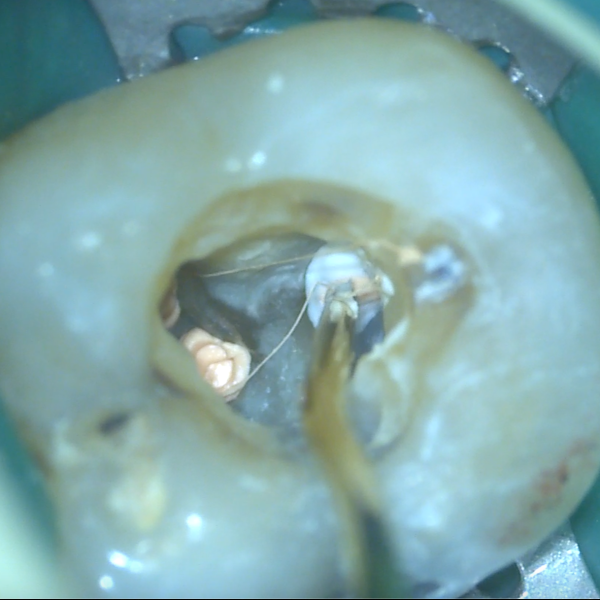

Shrnutí kalcium silikátových sealerů a potřebného vybavení pro rychlé a efektivní zaplnění kořenových kanálků pomocí pístové techniky:

• Jaké sealery jsou vhodné?

• Hrají roli kanyly?

• Z čeho může být zhotoven píst?

• Jak moc tlačit?

• Jak velké je riziko extruze materiálu a kdy není pístová technika vhodná?

Přednáška poskytne praktické informace a návody, které vám usnadní práci a pomohou se vyhnout komplikacím.